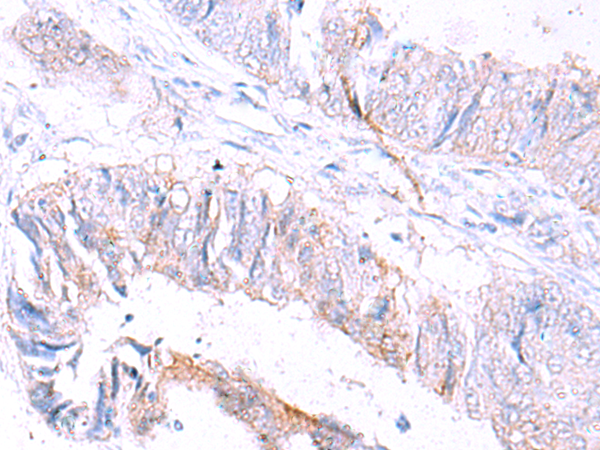

分类: 科研抗体货号: P11041别名: LPH, MSH, NPP, POC, ACTH, CLIP应用: WB,IHC反应种属: Human, Mouse